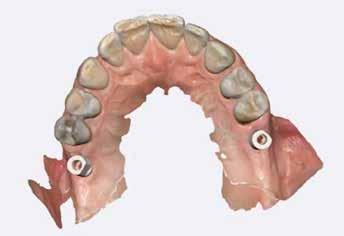

Az alábbi – négy esetből álló – sorozatban a CERALOG rendszert (BioHorizons Camlog) alkalmaztuk, és szóló foghiányok kerültek ellátásra. A CERALOG implantátumok Y-TZP-ből készülnek (10). A CERALOG rendszer minden szükséges elemet biztosít ahhoz, hogy bármilyen típusú pótlás megtartását lehetővé tegye ezeken az implantátumokon, az egyedi koronáktól a teljes ívre kiterjedő pótlásokig.

Az alábbi esettanulmányhoz négy pácienst választottunk ki (1. táblázat). Minden esetben egy, vagy több fog pótlására volt szükség, amelyhez kerámiaimplantátumokat használtunk. Valamennyi páciens általános egészségügyi állapota jó volt.

A sebészeti eljárás

Mind a hat implantátum esetén kétlépcsős műtétet végeztünk. Minden sebészeti eljárást bódítás, illetve preoperatív szisztémás antibiotikus terápia nélkül végeztünk. A négy eset közül kettőnél leukocitában és vérlemezkében gazdag fibrint (L-PRF) alkalmaztunk a beavatkozás során (IntraSpin, BioHorizons; 2. táblázat). Minden esetben a pontos CERALOG menetvágási (maximum 15 ford./perc) és fúrási (maximális fúrási fordulatszám: 550–800 ford./perc) protokollt követtük. Az összes implantátumot manuálisan helyeztük be 35 Ncm maximális nyomatékkal. Az implantátumokba PEEK zárócsavar került (2. ábra). A lágyszövetet atraumatikus, felszívódó varrattal, szorosan zártuk/összevarrtuk. A műtétek után szövődmények nem jelentkeztek. A pácienseket arra kértük, hogy a műtét utáni héten naponta kétszer öblögessenek klórhexidinnel (PERIO-AID, 0,05%, DENTAID). Az alsó állcsontnál három hónapos, a felső állcsontnál öt hónapos gyógyulási időt vettünk figyelembe. Három hónap (1. eset) és öt hónap (2., 3. és 4. eset) elteltével a műtétek második stádiumát helyi érzéstelenítés mellett végeztük. A gyógyu-

lási csavarokat (PEEK titáncsavarral) maximum 15 Ncm-rel húztuk meg (3–6. ábra). Az összes implantátum kiváló stabilitást mutatott (a mérésekhez Periotestet használtunk, a Medizintechnik Gulden jóvoltából), és teljesen osszeointegrálódott. Ezt a radiológiai vizsgálatok is megerősítették.

2a 3a 4a 2b 3b 4b 2c 2d Pozíció Implantátum átmérő Implantátum hossz L-PRF Behelyezési nyomaték Eset 1 #35 4 mm 12 mm Nem 35 Ncm Eset 2 #25 4 mm 12 mm Nem 30 Ncm #26 4 mm 8 mm Nem 25 Ncm Eset 3 #16 4 mm 8 mm Igen 25 Ncm #26 4 mm 10 mm Igen 30 Ncm Eset 4 #26 4 mm 10 mm Igen 30 Ncm

2. a–d ábra: PEEK zárócsavarok az implantátumokba helyezve, 1. eset (a). 2. eset (b). 3. eset (c), 4. eset (d). 3. a–b ábra: Röntgenfelvételek három hónap után (a) és a gyógyulási csavarok behelyezve (b, 1. eset). 4. a–b ábra: Röntgenfelvételek öt hónappal később (a) és a gyógyulási csavarok behelyezve (b, 2. eset). 2. táblázat: Az implantátum tulajdonságai.